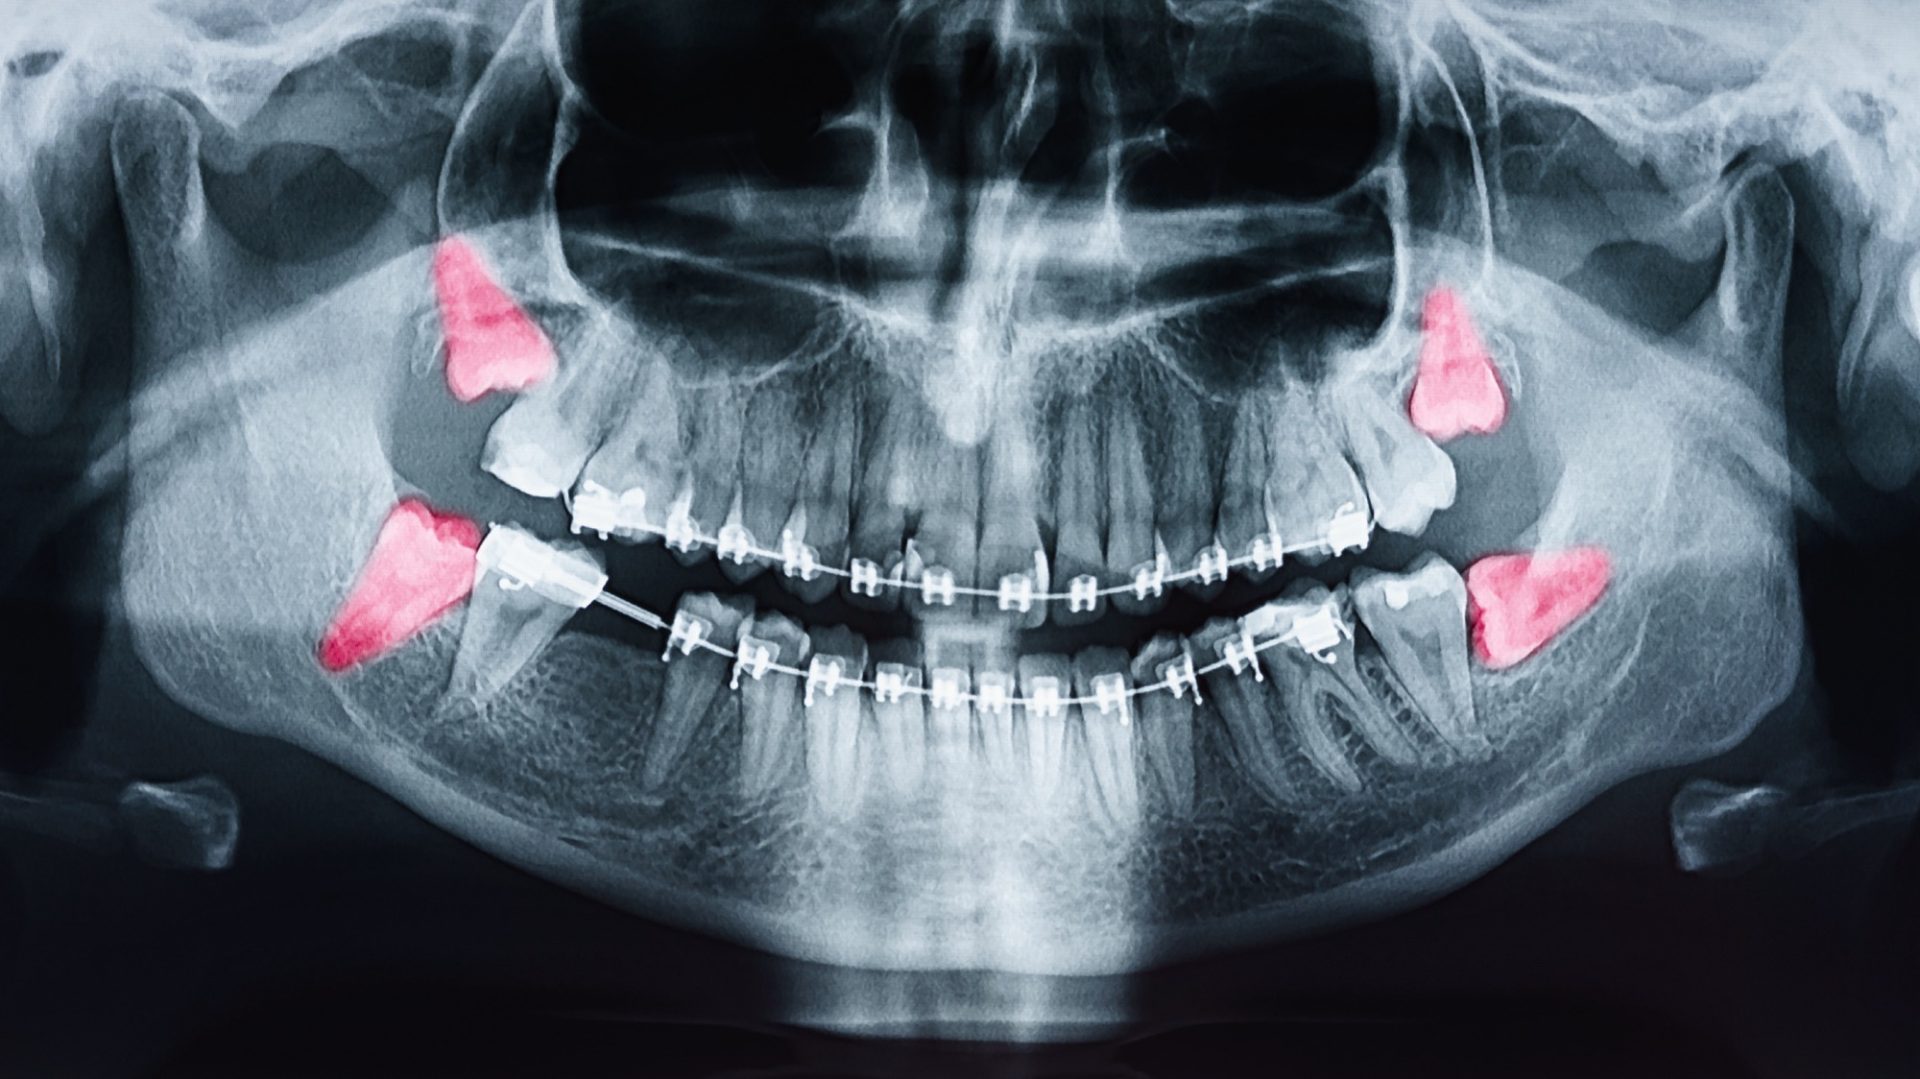

Before the procedure, your dentist will assess your wisdom teeth through X-rays to determine their position and the complexity of the extraction. You’ll be advised to fast for several hours before the surgery, especially if you’ll be receiving sedation. Make sure to arrange for someone to drive you home after the procedure since anesthesia may impair your ability to operate a vehicle.